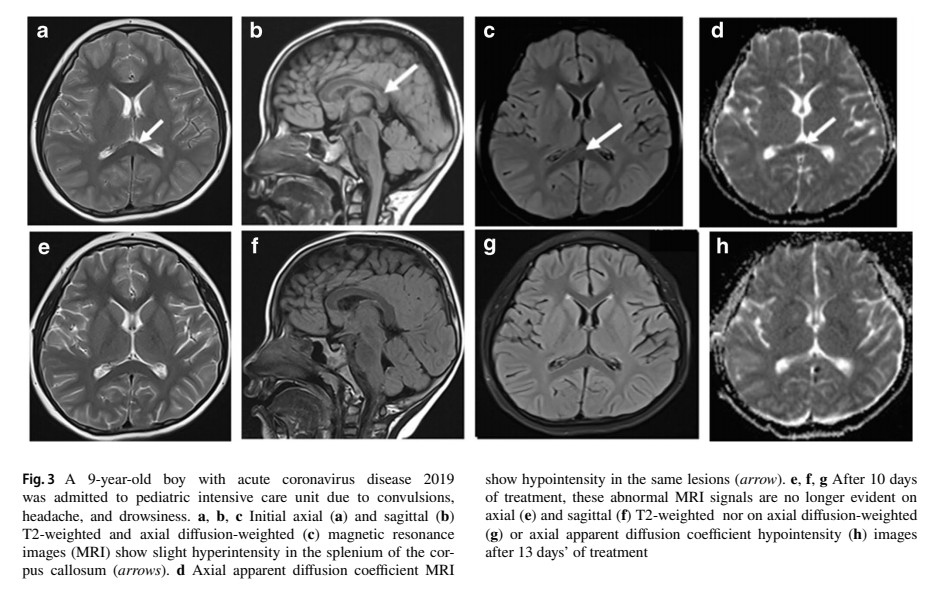

๐˜ฝ๐™ง๐™–๐™ž๐™ฃ ๐™ข๐™–๐™œ๐™ฃ๐™š๐™ฉ๐™ž๐™˜ ๐™ง๐™š๐™จ๐™ค๐™ฃ๐™–๐™ฃ๐™˜๐™š ๐™ž๐™ข๐™–๐™œ๐™ž๐™ฃ๐™œ ๐™›๐™ž๐™ฃ๐™™๐™ž๐™ฃ๐™œ๐™จ ๐™ž๐™ฃ ๐™˜๐™๐™ž๐™ก๐™™๐™ง๐™š๐™ฃ ๐™ฌ๐™ž๐™ฉ๐™ ๐™ฃ๐™š๐™ช๐™ง๐™ค๐™ก๐™ค๐™œ๐™ž๐™˜๐™–๐™ก ๐™˜๐™ค๐™ข๐™ฅ๐™ก๐™ž๐™˜๐™–๐™ฉ๐™ž๐™ค๐™ฃ๐™จ ๐™ค๐™› ๐˜พ๐™Š๐™‘๐™„๐˜ฟ-19 (๐™Š๐™ข๐™ž๐™˜๐™ง๐™ค๐™ฃ ๐™ซ๐™–๐™ง๐™ž๐™–๐™ฃ๐™ฉ) ๐Ÿ˜จ

Image

2) This study analyzed brain MRI findings in 102 pediatric patients infected with Omicron who were admitted to PICUs with neurological complications. The average age was 5.8 years and most patients were male. Common symptoms included fever, convulsions and altered consciousness. Image

3) MRI was performed 1-12 days after symptom onset in 93 patients. Abnormal neuroimaging findings were seen in 74% of cases. The most common finding was acute necrotizing encephalopathy seen in 48% of cases with abnormal MRI. This involved lesions in the thalamus, brainstem ... Image